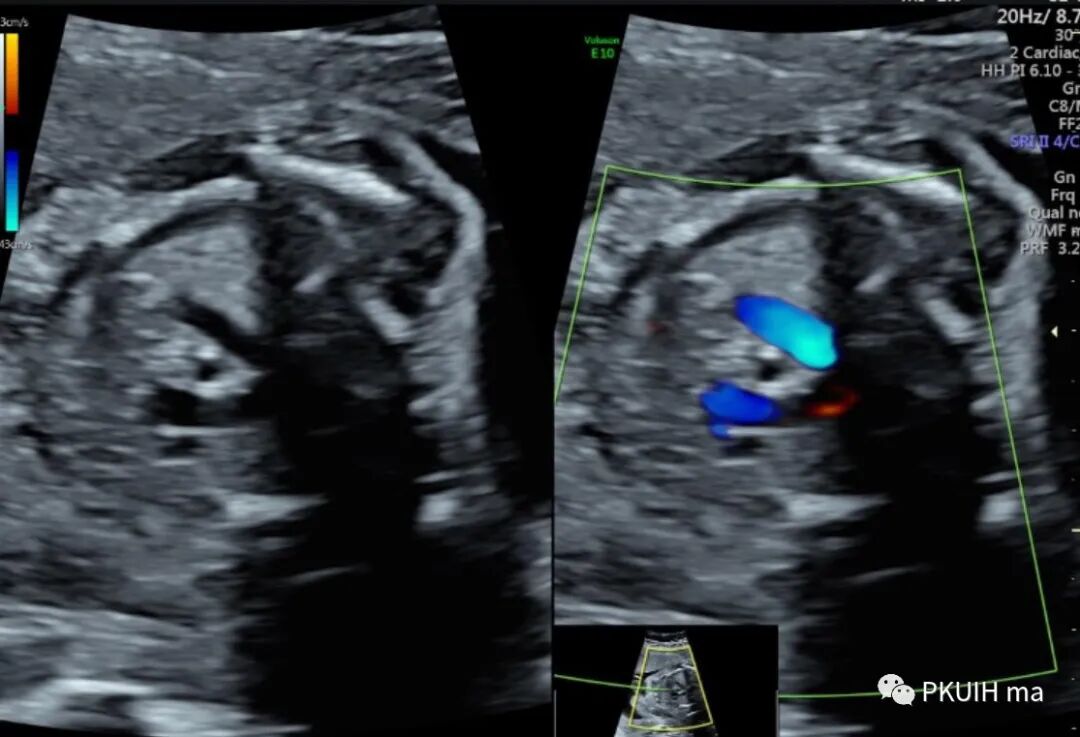

锁骨下动脉观察一般在主动脉弓水平横切面观察,显示左右锁骨下动脉像弓箭样向左右肩部走形。对于迷走的锁骨下动脉观察需要在三血管气管切面和主动脉冠状切面观察。右锁骨下动脉迷走在三血管气管切面可见一血管于主动脉弓降部发出自脊柱前方气管后方向右肩走行,在主动脉冠状切面显示主动脉弓降部见一血管迂曲向右肩部走行,频谱显示为动脉频谱。右锁骨下动脉迷走在三血管气管切面要和左无名静脉鉴别,左无名静脉汇入上腔静脉,频谱为静脉频谱,同时右锁骨下动脉也要和走形于气管后方汇入上腔静脉的奇静脉相鉴别,血流频谱有助于两者鉴别。

脊柱前方一红色血管为迷走的右锁骨下动脉,频谱为动脉频谱

冠状切面显示右锁骨下动脉起于主动脉弓降部(ARSA:迷走的右锁骨下动脉,LSA:左锁骨下动脉)

ARSA较多见,常认为是一种正常的变异。超声很容易诊断,观察时建议把血流标尺降到15-20cm/s,也可以采用三维超声多平面观察或四维血流显像模式辨认。发现右锁骨下动脉迷走时建议做心内外系统全面扫查。单纯的锁骨下动脉迷走如果不合并染色体异常一般无临床意义,出生后预后良好。由于单纯锁骨下动脉迷走不形成完整血管环,临床上常无明显症状,仅有极少数病例报道患儿有吞咽困难或呼吸困难。迷走的右锁骨下动脉还可能会压迫喉返神经,导致神经麻痹,这种情况称为 Ortner 综合症。因此,临床中发现锁骨下动脉迷走时要注意观察迷走的血管与气管和食管的关系,食管后型最常见(80%),其次是气管、食管间型(15%),最后是气管前型(5%)。ARSA合并21-三体有文献报道,同时ARSA也出现在其他一些染色体非整倍体异常中;同时ARSA也可合并一些心脏的锥干畸形,此时要注意22q11微缺失的染色体异常风险。